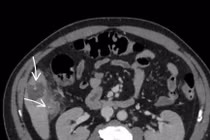

Trong khi mổ, ê kíp phẫu thuật phát hiện ổ bụng của bệnh nhân có dịch đục và bị nhiễm trùng nặng. Vùng tiểu khung, ruột thừa vị trí hố chậu phải viêm xung huyết. Một ổ áp xe tại đoạn ruột non vị trí cách góc hồi manh tràng khoảng 1 mét, nguyên nhân là mảnh xương cá dài 4 cm đâm thủng ruột non. Cách đó 10 cm, có một túi thừa Meckel lớn.

Các bác sĩ đã cắt bỏ ruột thừa viêm, cắt đoạn ruột non chứa túi thừa và ổ áp xe, làm sạch ổ bụng. Sau phẫu thuật 2 ngày, bệnh nhân hồi phục tốt và sẽ sớm được xuất viện.